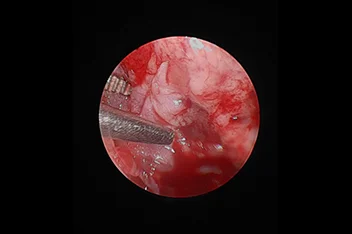

종양절제술

• 뇌종양

• 척수종양